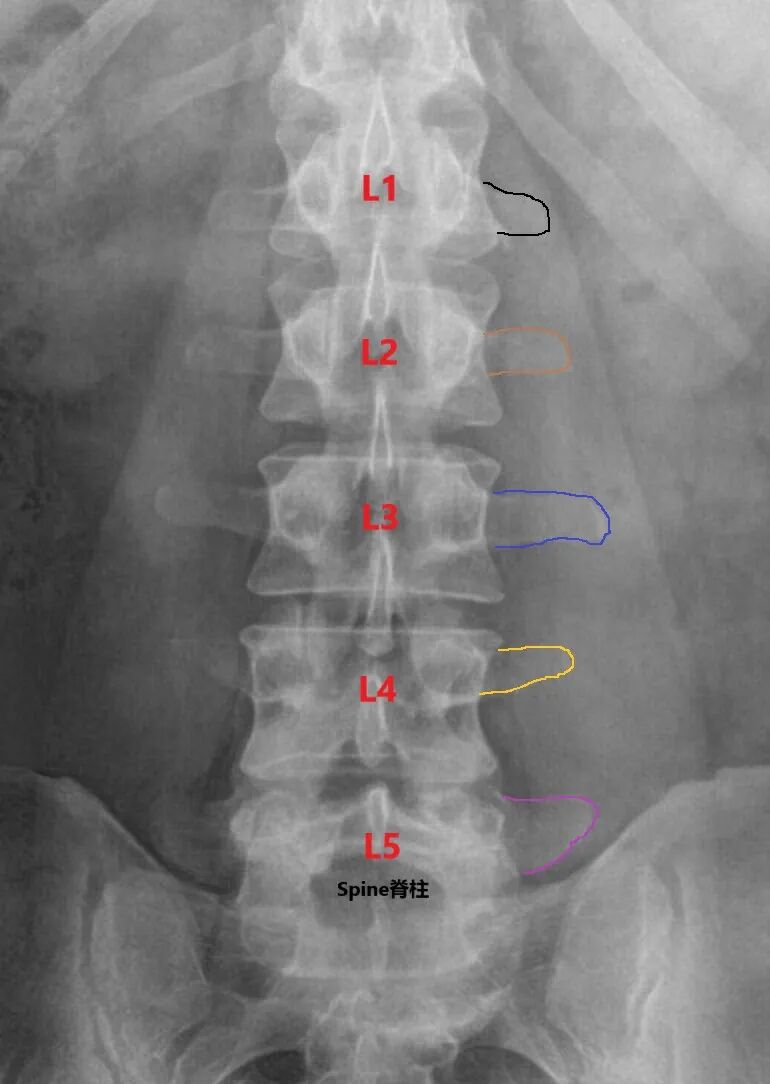

正常脊柱有12个胸椎,5个腰椎ICL:髂嵴连线

不典型脊柱可有11个胸椎,6个腰椎(T12相当于L1,胸椎腰化)

不典型脊柱可有13个胸椎,4个腰椎

不典型脊柱可出现腰骶移行椎(Lumbosacral Transitional Vertebrae,LSTV)

LSTV椎体同时具有腰椎和骶椎的特点,其在临床上很常见,整个人群的发生率为4-37%(很高的比例)尤其存在Ⅲ和Ⅳ型LSTV,胸腰椎术中很容易定错责任节段。有些医生,术前就一个MRI片子,就给患者做PVP或PKP了,对于伴有多节段陈旧性骨折患者可能会定错节段。开会听课的时候,北京协和医院和上海华山医院的专家提到过,他们要求每个脊柱手术的患者都应该有脊柱6张X线片 (正侧位、动力位和双斜位)、CT和MRI,这是有道理的,除了留全资料,可能更重要的是能避免误诊漏诊一些问题。

节段定位,常以肋骨、骶椎和横突为标志物。肋骨定位时,必要时参考胸片。横突常以其解剖特点定位,腰椎横突“三长、四翘、五宽”,即L3横突最长,L4横突上翘,而L5横突是最宽的比如存在骶椎腰化(6个腰椎),可以结合X线和MRI中骶椎形态,明确椎间盘突出的节段;再比如骨质疏松性椎体压缩骨折,需结合X线术前明确责任椎体的形态,离最下肋骨或骶椎隔了几个椎体,因为术中你是在C臂下定位的,一次透视看不到骶椎至胸椎。警惕仅仅有一个MRI片子,MRI上认为的L1轻微骨折或L1严重骨折伴多发椎体楔型变,术中就直接C臂看到最下肋骨下面哪个椎体或者骶椎往上数第5个椎体就注射骨水泥了。如果碰到不典型脊柱,可能就会做错节段。